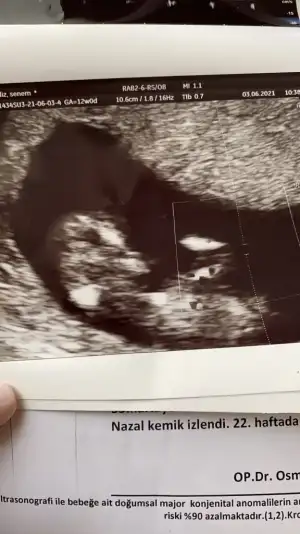

dr soylemeden siz gorun genital nub teorisi ( bebegin cinsiyeti)

Nuba göre kız mı erkek mi sizce kızlar?